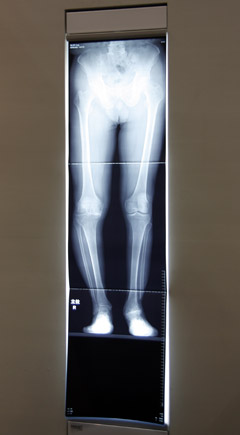

Safire Galleryに展示されたスロットラジオグラフィの画像

● 最長120cmの長尺撮影機能を搭載した「RADspeed safire」

デジタル式一般撮影システム「RADspeed safire」では,新たに長手方向に最長120cmの画像を取得できる長尺撮影を発表した。FPDを移動させながら,X線管の角度を変えて広い視野をカバーする。約10秒で撮影が終了し,その約10秒後につなぎ合わせた画像を自動で表示。つなぎ目の目立たない高精度な画像を取得できるという。